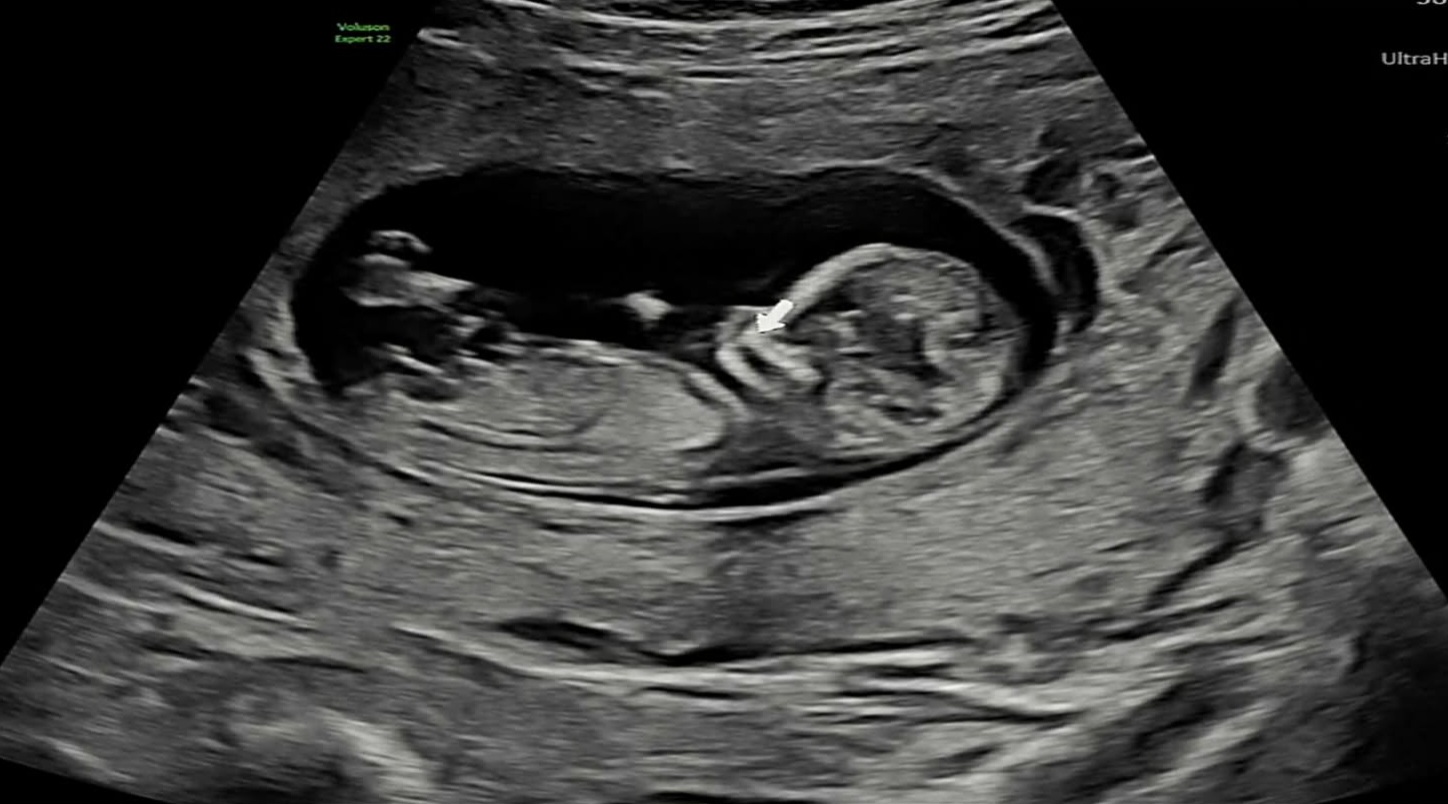

셋째 성별각도 궁금해요 전에껀 잘못올렸어요

12주1일에 갓을때 정확하진 않지만 아들같다고 하셧는데 맞을까요 ㅜㅡㅜ 3살터울 남매 키우고 잇는데 아들이 너무 활발하네요🤣